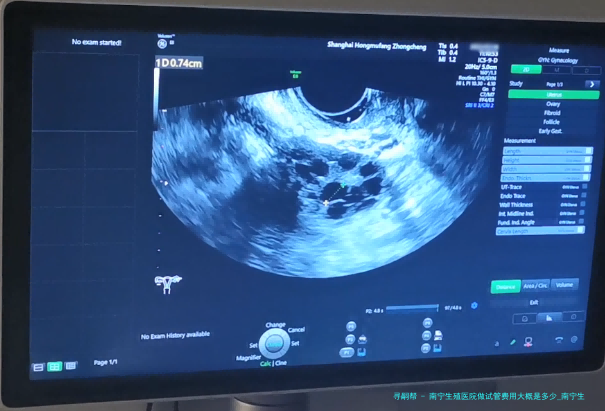

南宁生殖医院做试管费用大概是好多?试管婴儿已然成为许多不孕夫妻实现生育愿望的重要方法其中之一。南宁生殖医院作为专门从事辅助生殖医学的医疗机构,为不孕夫妇提供了精良的试管婴儿服务。如此南宁生殖医院做试管费用大概是几何呢?接下来将细致说明。

在了解详细的试管费用前,我们先来了解一下试管婴儿费用的组成。平常试管婴儿手术所牵涉到的费用囊括下列数个方向:基本治疗费、辅助检查和药品费、手术设备使用费、麻醉师操作费等。

首先是基本治疗费,这片面包括了整个试管过程中所需的医护服务以及专家团队的助力工作。其次是辅助检查和药物费,这部分囊括了对夫妻进行全方位检查所需的各项项目以及实施治疗所需的药品费用。然后是手术设备使用费,这部分囊括了试管婴儿手术所需的各式各样器材和设备的费用。最后是麻醉大夫操作费,这部分包括了在试管手术过程中为患者提供麻醉服务的费用。

南宁生殖医院作为一家专业从事辅助生殖医学的医疗单位,提供了全面而专业的试管婴儿服务。根据不同病人的详细情况和需要,试管费用可能会有所差别。通常来说,南宁生殖医院做试管的基本治疗费大约在5000-10000元之间。辅助检查和药物费、手术设备使用费、麻醉师操作费等其他费用视详尽情形而定。

下方是南宁生殖医院区分试管项目的详细费用参考表。

项目费用(元)

基本治疗费5000-10000

辅助检查和药品费3000-5000

手术器械使用费2000-3000

麻醉师操作费500-1000

请关注,之上费用仅作参考,具体费用于南宁生殖医院实际收费为准。